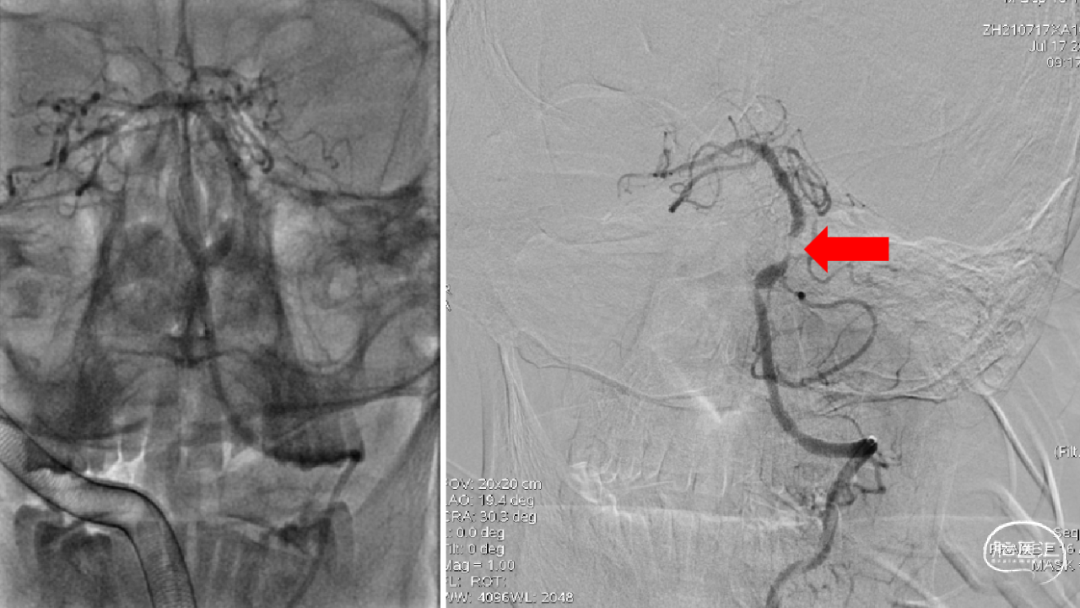

DSA造影

1、选择右侧椎动脉入路;2、造影提示V4段近端狭窄,远端未见显影。

1、ACE60抽吸导管插至右侧椎动脉V4段,微导丝导丝反复尝试未能越过闭塞段;2、考虑右侧椎动脉V4段远端完全闭塞。

右侧颈动脉造影未见明显后交通开放,可见基底动脉末端显影(红色箭头)。